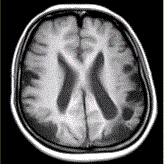

问题 女性,22岁。癫痫发作及智力异常。MRI显示见下图。 有关该病的描述正确的是(提示MRA所示如图。)

选项 A.双侧颈内动脉及其分支部分闭塞 B.双侧大脑后动脉狭窄、部分闭塞 C.颅底可见大量侧支循环形成 D.血管未见明显异常 E.双侧椎动脉显示清晰 F.双侧颈内动脉显示清晰

答案 ABC